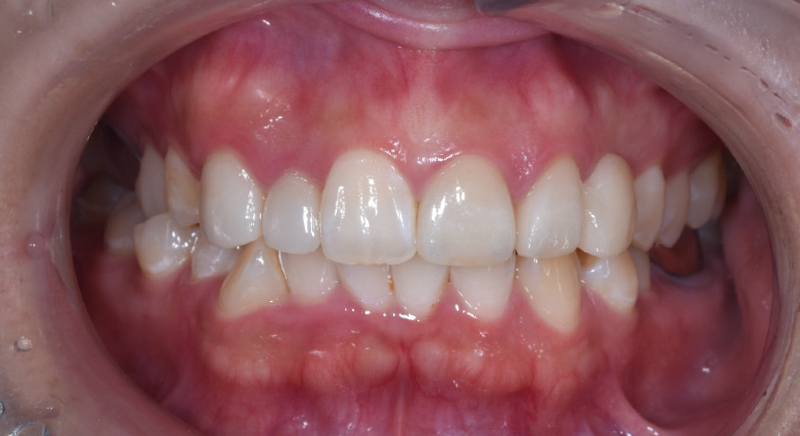

case2

術前

術後

| 主訴 | 前歯の形が気になるので綺麗にしたい |

|---|---|

| 治療内容 | 審美性を回復させるために上の前歯5本の歯を一層削合し、型取りを行った。 一度形を最終確認し、型どりから約2週間後完成したセラミックの被せ物とブリッジを装着した。 |

| 治療費用 | 718,740円(税込) |

| 治療期間 | 3か月 |

| 治療のリスク | 治療によっては歯の体積を削る量が多い場合があります。 |

| 治療の副作用 | 治療後、軽い出血や痛みを伴う可能性があります。 稀にセラミックが欠ける場合があります。 |